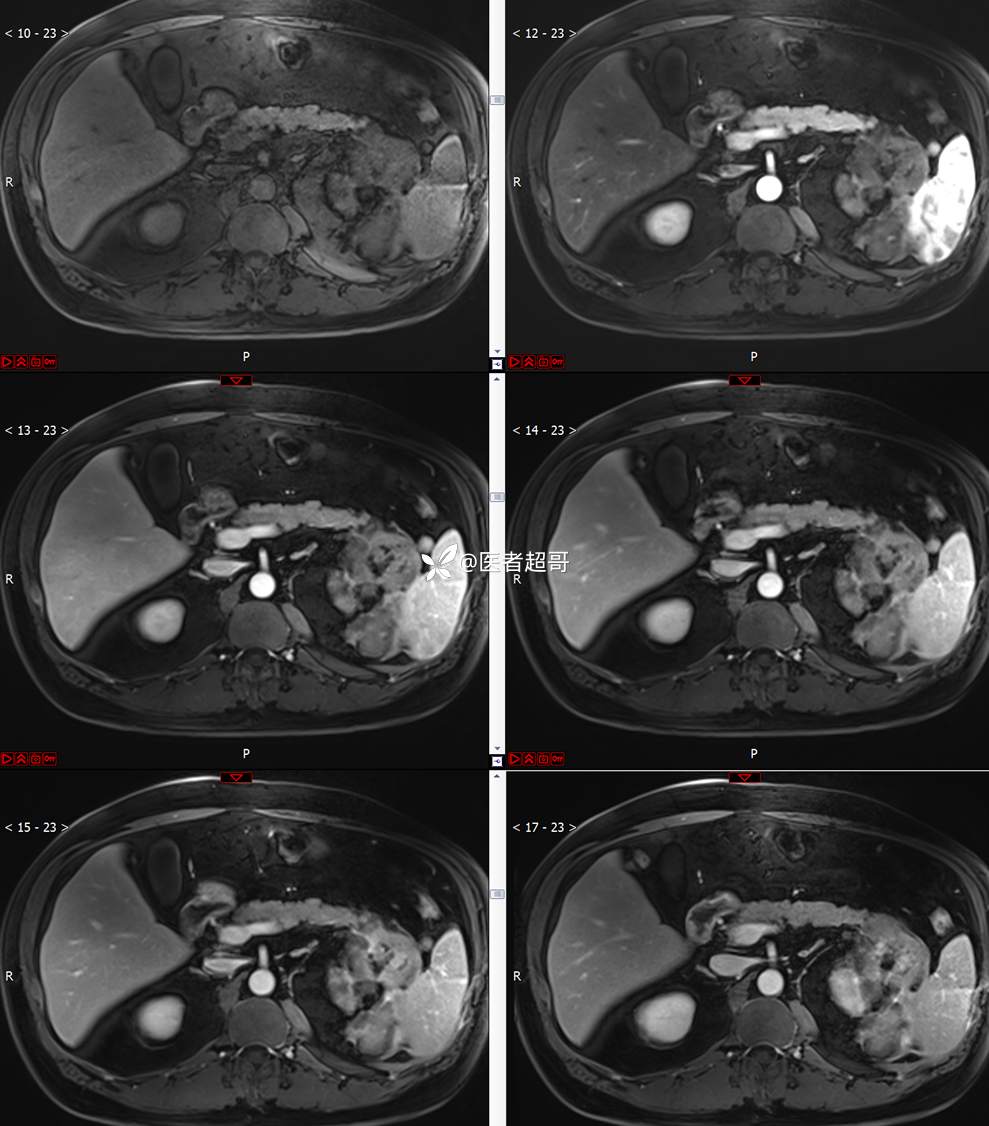

主 诉:查体发现左肾肿物9天。

现病史:患者9天前于附属医院行常规腹部CT检查时,发现左肾占位性病变并肾周脂间隙软组织增多,自述无明显腰腹部不适,无尿频、尿急、尿痛及肉眼血尿,未予特殊治疗,患者近期无头晕头迷,胸闷气急,腹胀腹泻及其他部位明显不适,遂至我院就诊,门诊以“肾肿物”收入院,患者自发病以来,精神可,睡眠饮食可,大便正常,体重无明显减轻。